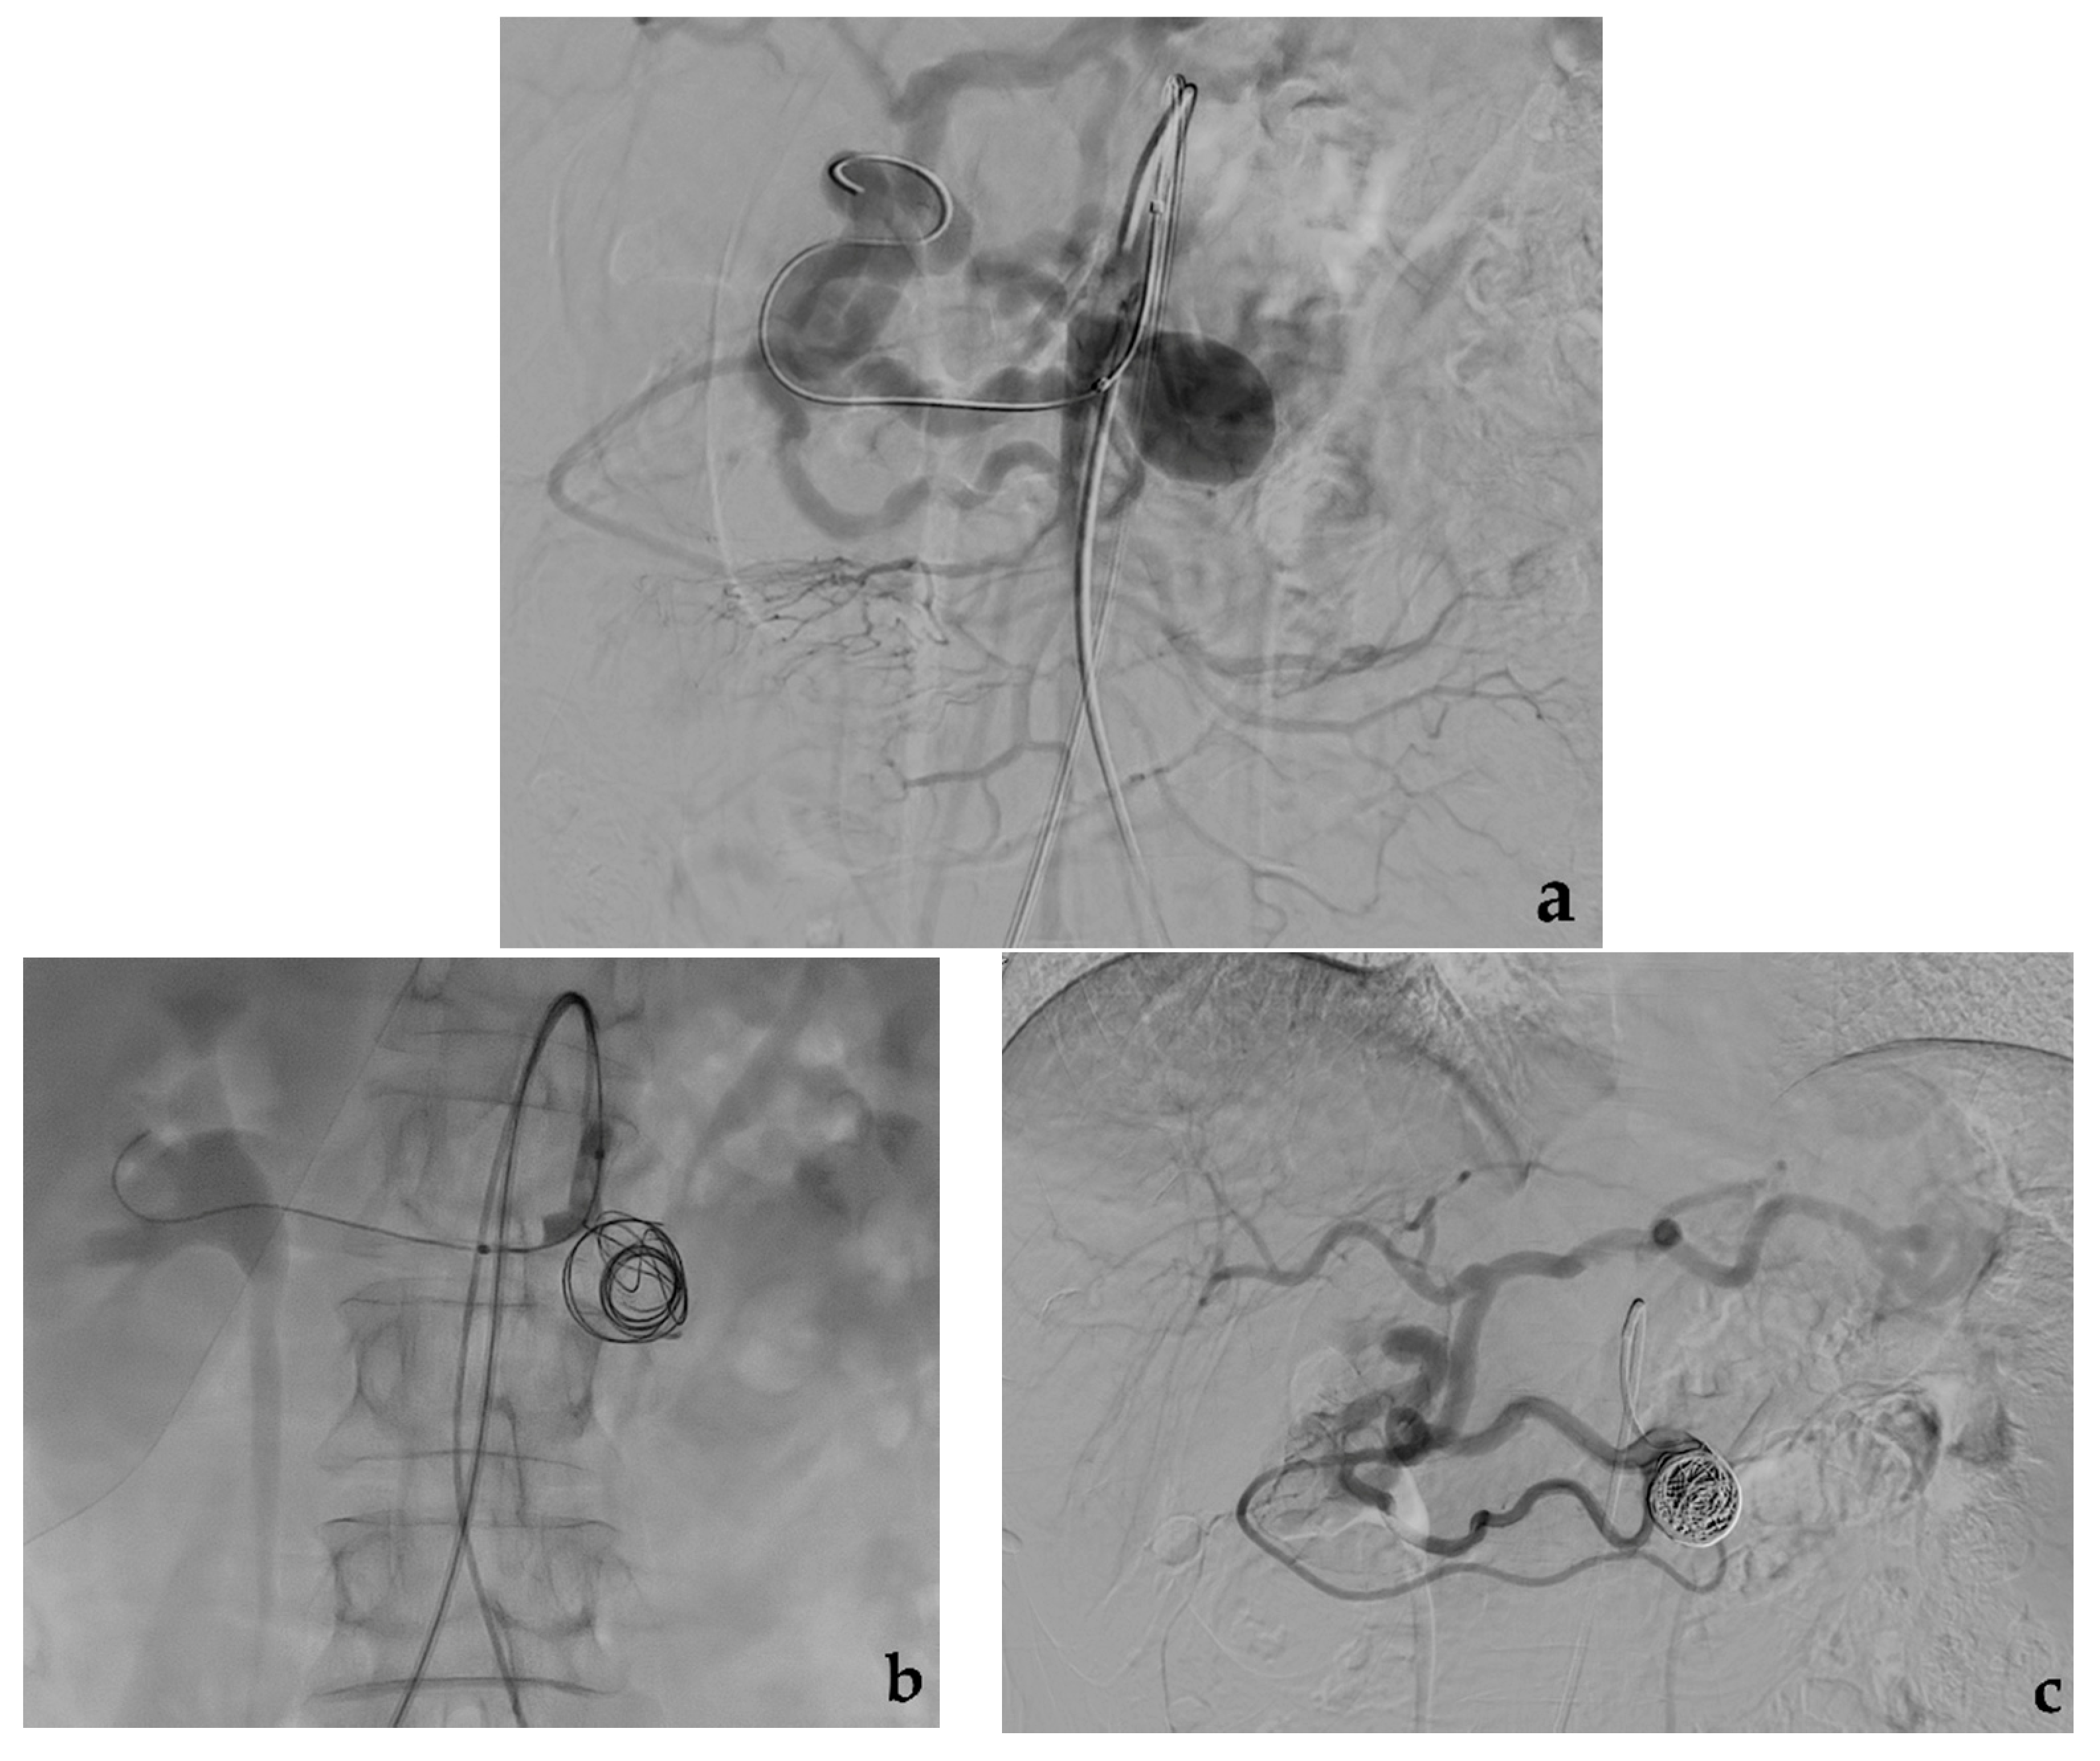

3.1. Coil Embolization

- Yasumoto, T.; Osuga, K.; Yamamoto, H.; Ono, Y.; Masada, M.; Mikami, K.; Kanamori, D.; Nakamura, M.; Tanaka, K.; Nakazawa, T.; et al. Long-term outcomes of coil packing for visceral aneurysms: Correlation between packing density and incidence of coil compaction or recanalization. J. Vasc. Interv. Radiol. 2013, 24, 1798–1807. [Google Scholar] [CrossRef] [PubMed]

- Yamamoto, S.; Hirota, S.; Maeda, H.; Achiwa, S.; Arai, K.; Kobayashi, K.; Nakao, N. Transcatheter coil embolization of splenic artery aneurysm. Cardiovasc. Interv. Radiol. 2008, 31, 527–534. [Google Scholar] [CrossRef]

- Wojtaszek, M.; Lamparski, K.; Wnuk, E.; Ostrowski, T.; Maciąg, R.; Rix, T.; Maj, E.; Milczarek, K.; Korzeniowski, K.; Rowiński, O. Selective occlusion of splenic artery aneurysms with the coil packing technique: The impact of packing density on aneurysm reperfusion correlated between contrast-enhanced MR angiography and digital subtraction angiography. Radiol. Med. 2019, 124, 450–459. [Google Scholar] [CrossRef]

- Yoon, T.; Kwon, T.; Kwon, H.; Han, Y.; Cho, Y. Transcatheter arterial embolization of splenic artery aneurysms: A single-center experience. Vasc. Spec. Int. 2014, 30, 120–124. [Google Scholar] [CrossRef] [PubMed]